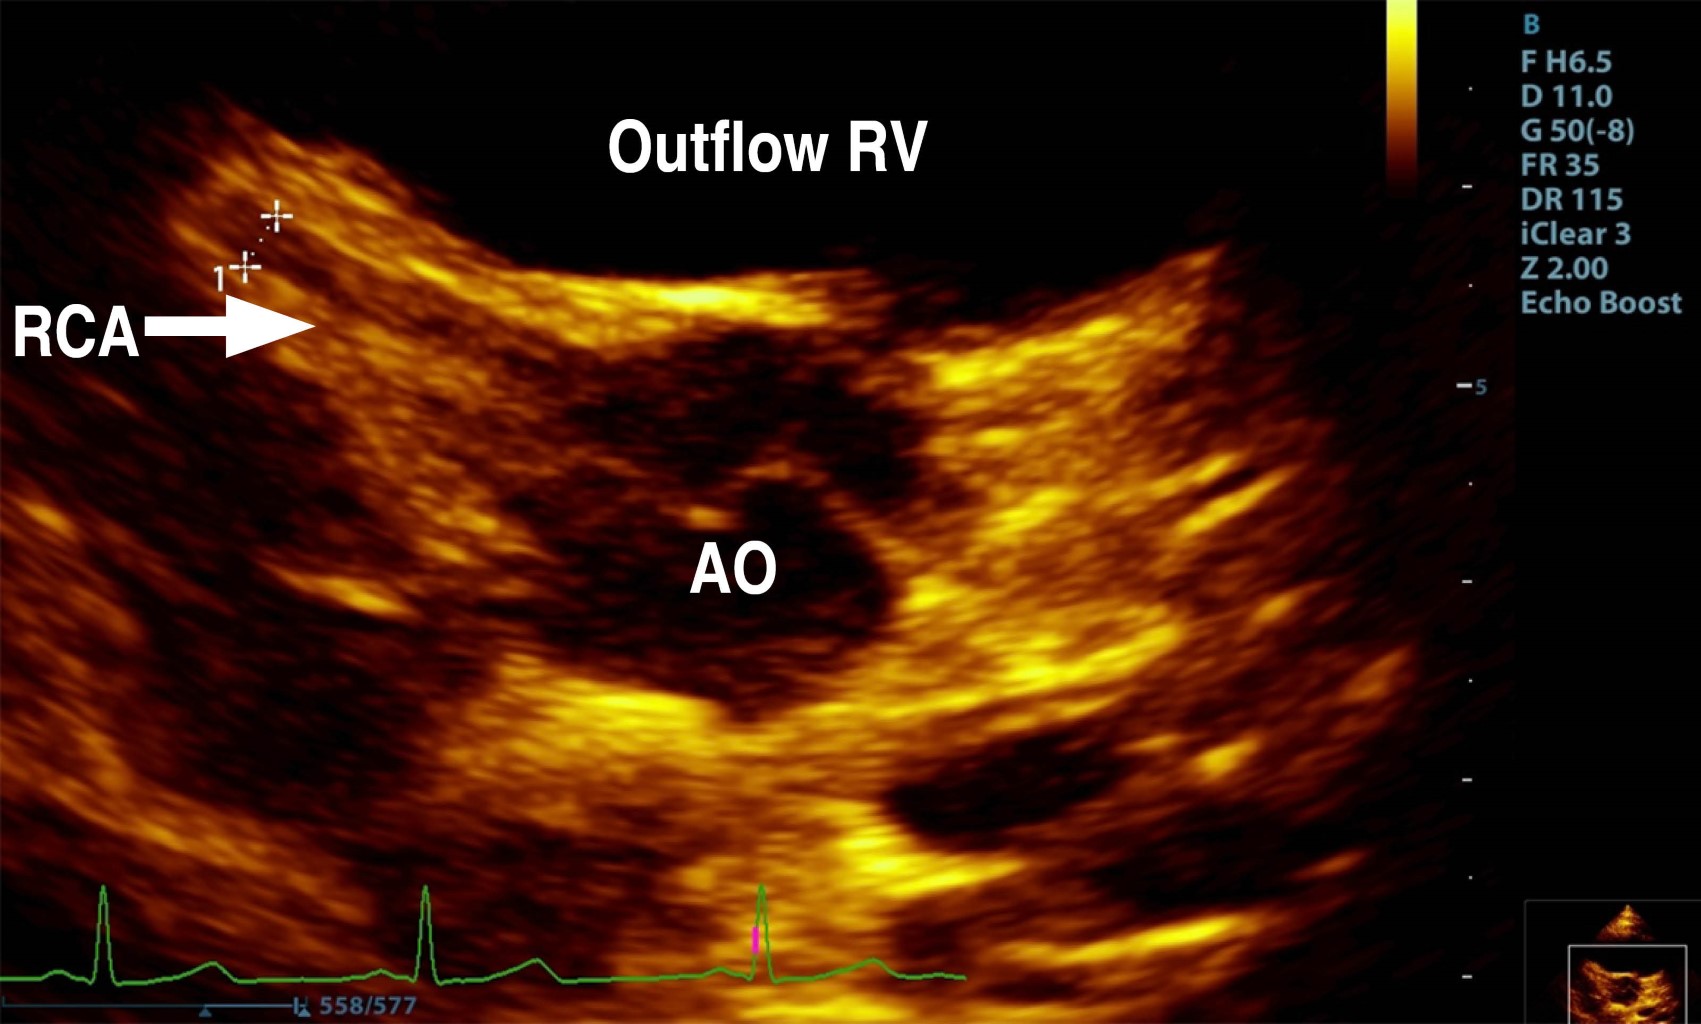

The parasternal short-axis view of the aortic root showed the right coronary artery (RCA) and left coronary artery (LCA) in their appropriate anatomical positions, with the proximal segment of the RCA exhibiting a Z score of 0.2 (Figure 1). However, the suprasternal longitudinal view identified an abnormal vascular structure with anterograde flow descending into the right branch of the pulmonary artery (RBPA) (Figure 2). The suprasternal short-axis view illustrated an anastomosis at the proximal segment of the RBPA, characterized by continuous, pulsatile flow, a maximum recorded velocity of 2.8 m/s, and a maximum gradient of 31 mmHg (Figure 3).